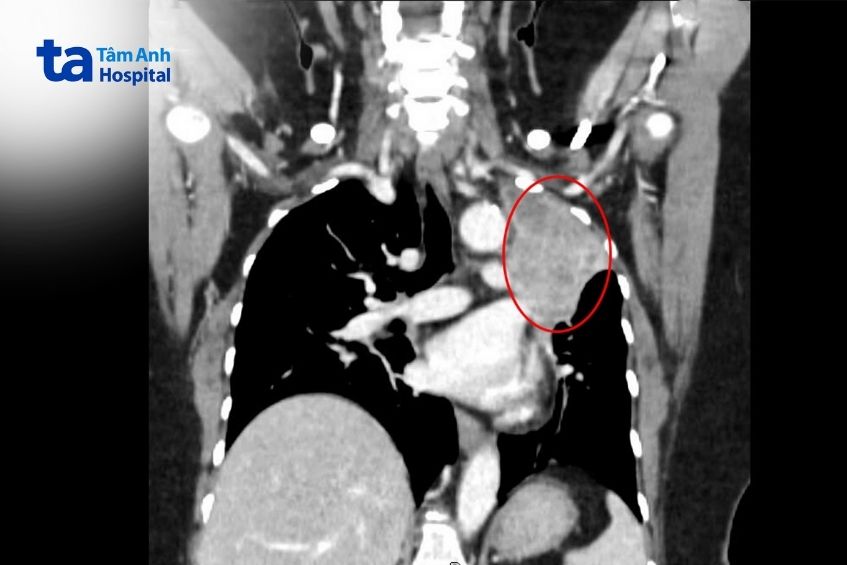

“Đây là nguyên nhân khiến bà Hoa xuất hiện các triệu chứng đau đầu, mất thăng bằng, tê yếu nửa người như đột quỵ”, bác sĩ Anh Thư cho biết, thêm rằng kết quả chụp CT lồng ngực tiếp tục ghi nhận thùy trên phổi trái của người bệnh có khối tổn thương kích thước hơn 7 cm, bờ gồ ghề, gây xẹp phổi xung quanh. Bà Hoa trước đây nhiều lần bị bệnh cảm sốt nhưng chỉ uống thuốc điều trị tại nhà. Lần gần nhất bà có vấn đề sức khỏe là bị hoa mắt, chóng mặt, ngất xỉu, nằm ngủ mê man 6 tiếng thì khỏe lại.

Sau hội chẩn, bà Hoa được ê kíp phẫu thuật thần kinh mổ não lấy trọn khối u 2,5 cm để giải áp nội sọ, giúp cải thiện các triệu chứng. Kết quả giải phẫu bệnh tổn thương ở não xác nhận ung thư biểu mô tuyến của phổi di căn não. Các kết quả kiểm tra sau đó tiếp tục ghi nhận bà Hoa bị di căn thêm ở gan, thượng thận, xương.